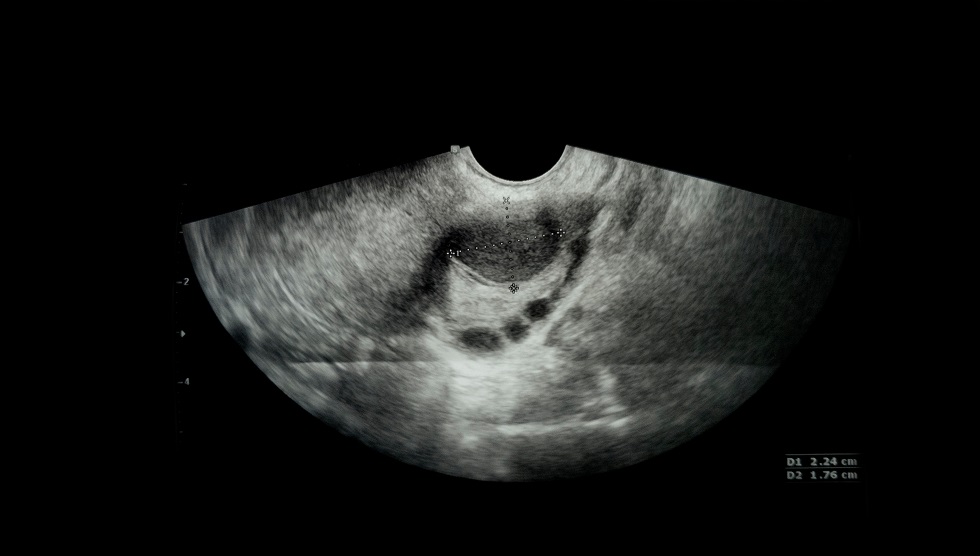

Dimensiunea chistului ovarian funcțional de 7 cm.

Prezența în structura în cazul chisturilor mai mari de 7 cm, efectuarea rmn permite aprecierea mai exactă a structurii pereților acestora.